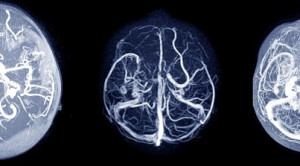

Aneurisma Intrakranial Tidak Ruptur: Konservatif atau Operatif

Pada aneurisma intrakranial yang tidak ruptur atau unruptured intracranial aneurysm, pendekatan tata laksana mencakup manajemen konservatif, kliping bedah mikro, dan coil endovascular....(Baca Selengkapnya)